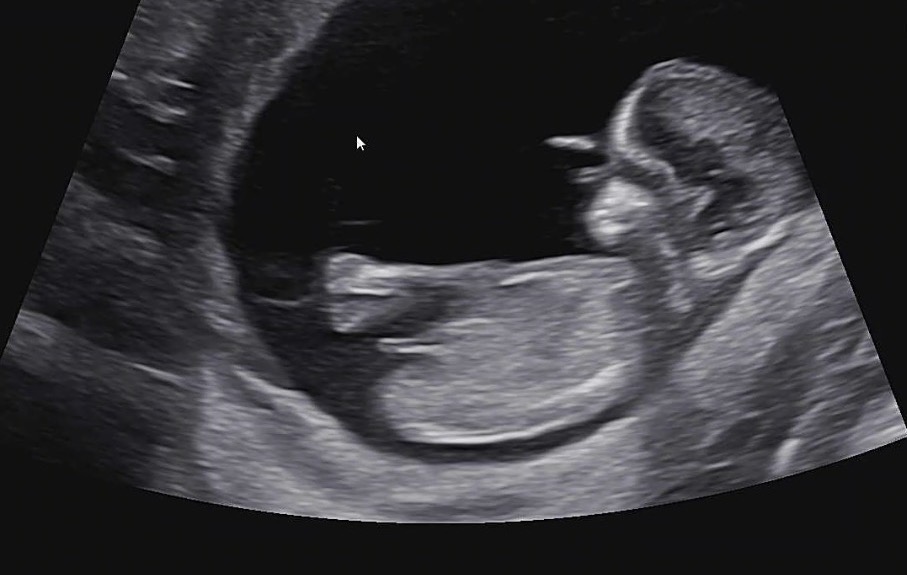

12주 1일 성별 투표 부탁드립니당 중간에 뭘까요 ..

태몽이나 느낌은 정말 딸로 생각했는데 중간에 무엇이 있는거 같아요 .... ㅎ🥺🥺